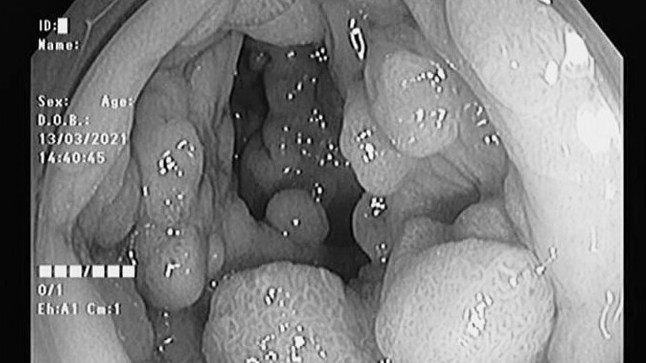

Hàng trăm polyp chen chúc trong đại trực tràng hai anh em

Bệnh ung thư -  18/03/2021

Các bác sĩ Bệnh viện Đa khoa Hùng Vương, ngày 15/3 nội soi đại tràng của hai người, nhận thấy hàng trăm polyp với nhiều kích cỡ từ 3 mm đến 2 cm, dày...